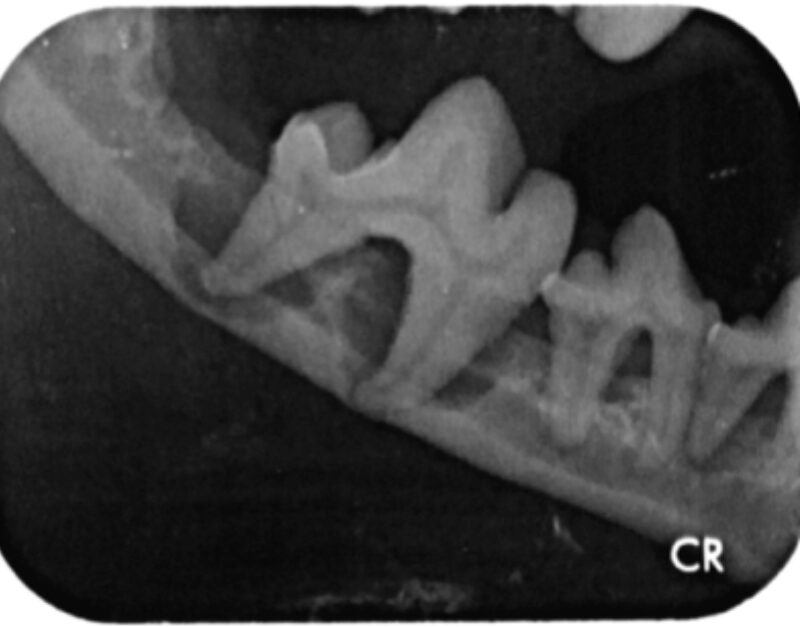

Weil wir von außen also nur einen Bruchteil des Zahns sehen können und schon gar nicht das Innenleben oder den Kiefer beurteilen können, ist das Zahnröntgen unerlässlich. Aber auch eine gute Sondierung des Zahnes und seines Gingivasulcus ist sehr wichtig, um Attachmentverluste und Furkationen im Zwischenwurzelbereich festzustellen. Dabei sollte jeder Zahn an mindestens vier Stellen sondiert werden (Abb. 6).

Zahnschmerzen werden leider oftmals unterschätzt. Der einzige Weg, um schmerzhafte Prozesse im Bereich der Zahnwurzeln zu erkennen, ist das dentale Röntgen und eine gründliche Aufnahme des gesamten Zahnstatus. Daher gehören zu jeder professionellen Zahnsanierung auch Röntgenaufnahmen aller Zähne mit ihren Wurzeln und die Sondierung aller Zähne an mindestens vier Stellen."

In Narkose sah man auf Leilas Röntgenbildern dann das gesamte Ausmaß ihrer Zahnerkrankung. Bis auf die Canini wiesen alle Zähne hochgradige Wurzelentzündungen mit Osteolysen des Kieferknochens auf. Deshalb konnte man auch schon von außen die Zahnhälse freiliegend sehen. Im Wurzelbereich waren die Veränderungen so schlimm, dass der Unterkiefer kurz vor einer Fraktur stand.

Es ist sehr wichtig zu verstehen, dass eine Zahnreinigung ohne Aufnahme eines kompletten Zahnstatus inklusive Zahnröntgen nichts weiter ist als eine kosmetische Behandlung, da krankhafte Prozesse übersehen werden (abb. 7-10).